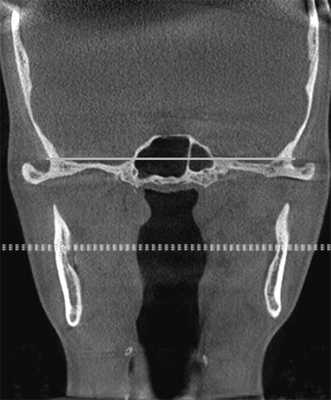

Кроме того, необходимо обращать внимание на симметричность расположения височных ямок при ориентации черепа по срединно-небному шву в корональной проекции, так как если они находятся на разных уровнях, то клинически врач увидит наклон нижней челюсти, что может свидетельствовать о скелетной ротации сфенобазилярного синхондроза — краниальный ROLL (рис. 4).

Рис. 4. Оценка симметричности височных ямок.